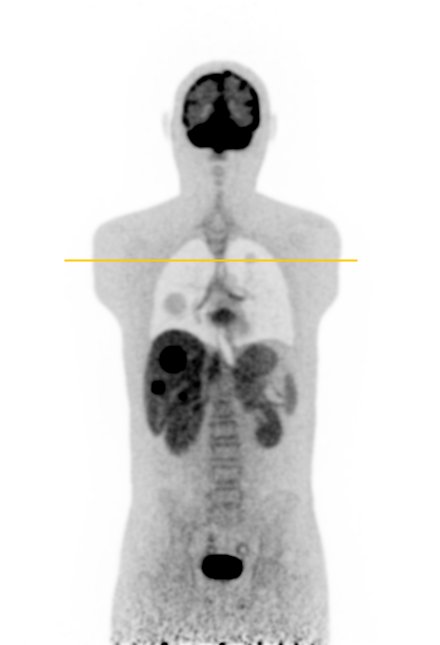

In this section, we present the results of our \acFDG-trained \acDLSE model applied to \acPSMA to evaluate its ability to generalise to radiotracers not included in the training data.

Figure 9 shows two clinical \acPSMA dataset examples. The first dataset illustrates a patient with a prostate lesion and shows good agreement between the \acDLSE and \acSSS corrected \acPET images for both the organs and the lesion.

The second patient example features two adjacent liver lesions; one with a higher and one with a lower activiy level compared to the background liver activity. The \acDLSE-corrected image shows higher activity levels in both the liver and the lesions. Based on a \ac3D manual segmentation of the liver and the FLAB segmentation of the lesions, the contrast values were found to be similar for \acDLSE and \acSSS, with values of and , respectively, for the necrotising lesion, and and , respectively, for the active lesion. These values compare with contrasts of and , respectively, in the non-scatter-corrected image.

| No correction | DLSE | SSS | Profiles |

![]() |

| Sex | Weight | Dose | Coincidences | |

| 1st row | Male | 82 kgs | 202 MBq | 743 millions |

| 2nd row | Male | 73 kgs | 198 MBq | 738 millions |

Finally, Figure 9 shows visually similar results between \acDLSE and \acSSS-corrected images. Furthermore, \acSUVmax values were found to be similar between the two methods (Figure 10). These results suggest that the method could adapt from one radiopharmaceutical to another without the need for retraining.